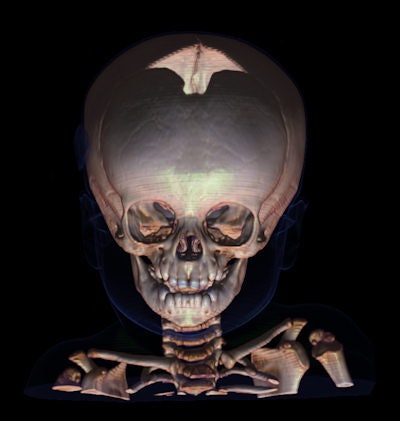

Les autopsies virtuelles peuvent jouer un rôle lorsque l'équipe médico-légale soupçonne un cas de maltraitance d'enfant. Sur cette image, le scanner crânien post mortem avec rendu volumique suggère une subluxation atlanto-axiale rotatoire. Veuillez remarquer la position de la masse latérale droite de la première vertèbre cervicale comparée à la colonne de masses latérales droites des vertèbres inférieures. Il s'agit d'une découverte non accidentelle dans plusieurs scanners post mortem. Images fournies avec l'aimable autorisation du docteur Anders Persson, PhD, Centre pour la science de l'imagerie médicale et la visualisation, Université Linköpings, Suède.Malgré un intérêt accru, des obstacles administratifs, légaux et financiers ont retardé l'adoption de cette technique par la France. Le gouvernement reconnaît qu'une autopsie virtuelle est un acte médical et a identifié des centres principaux, qui sont remboursés pour l'examen. Actuellement, c'est l'hôpital qui bénéficie du remboursement. Reste à savoir qui du personnel sera payé et pourquoi, a souligné le docteur Bernard Proust du Centre Hospitalier Universitaire de Rouen (CHU-Rouen).